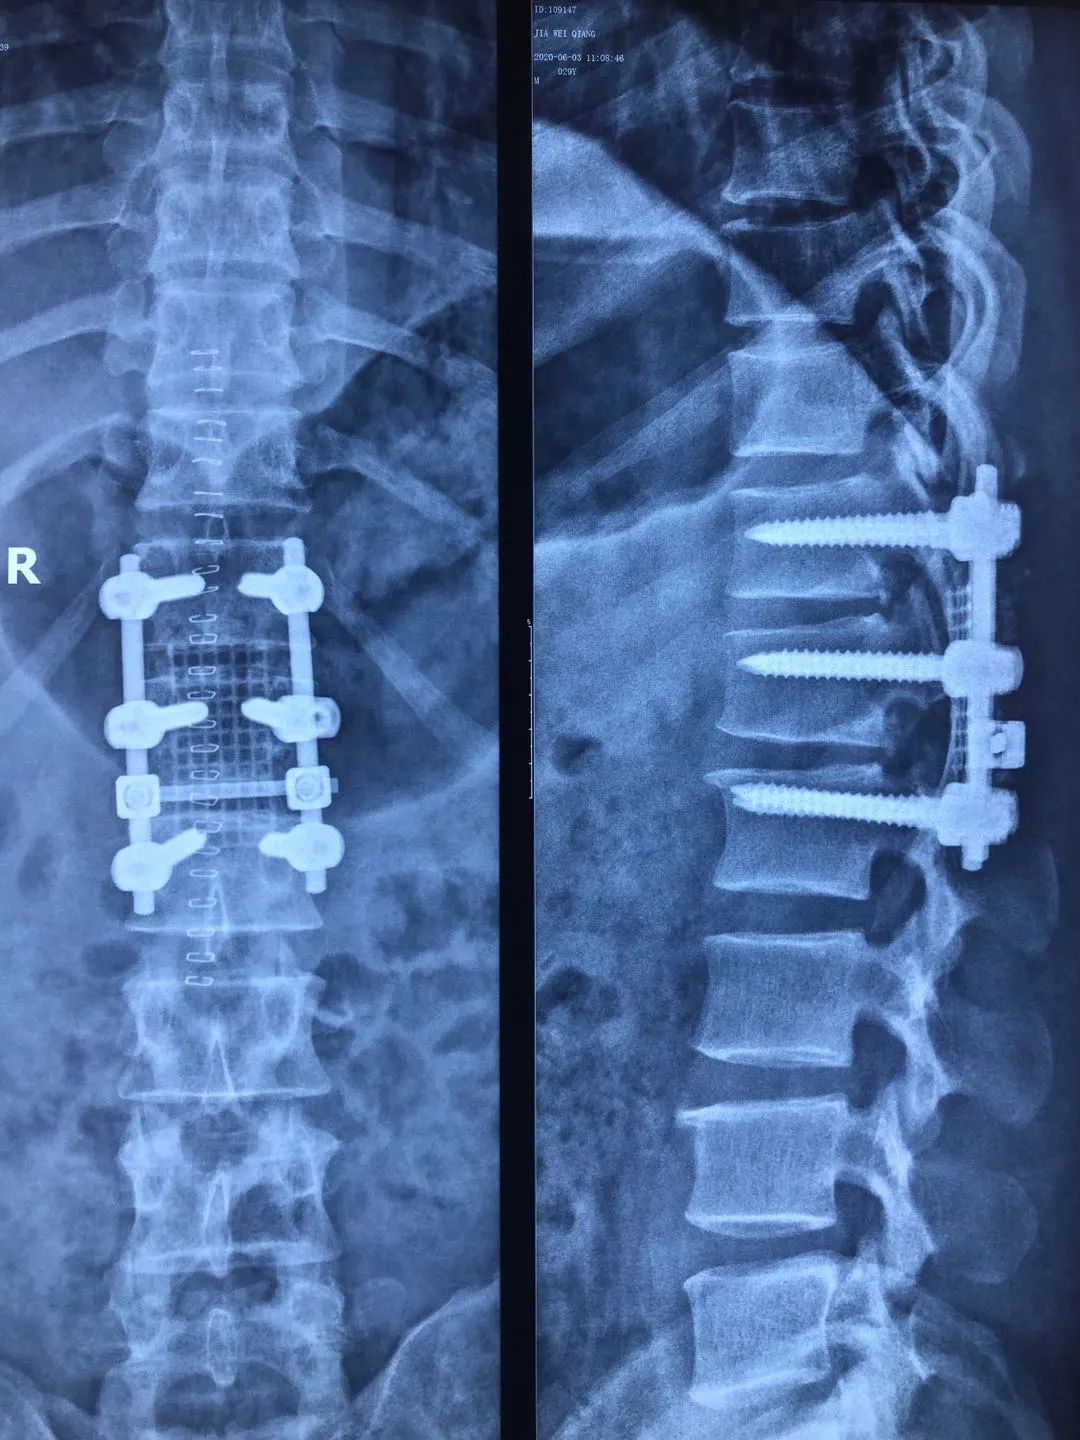

妙手回春显医术 患者感谢送锦旗——运城同德医院成功完成高位腰椎间盘突出手术